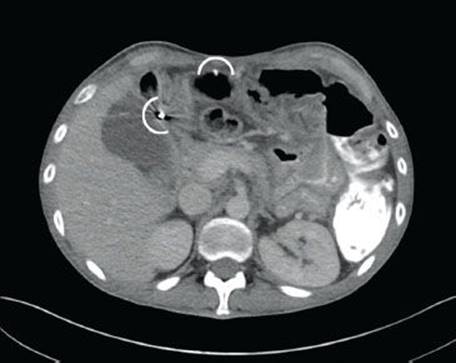

Figure 4.271 Endometriosis. This consultation case originated from a 25-year-old woman with a bleeding rectal mass. It was clinically ominous appearing, leading the surgeon to inform the patient that the lesion was most likely malignant. Based on the patient’s young age, the family asked for the case to be externally reviewed.

Endometriosis is the presence of at least two of the three following features outside of the uterus: endometrial glands, stroma, and hemorrhage (Figs. 4.271–4.273). Up to 37% of women with endometriosis have intestinal involvement, and any layer of the bowel can be involved. The clinicopathologic presentation is diverse and presentations can overlap with appendicitis, IBD, diverticular disease, infectious colitis, a surgical acute abdomen, malignancy.125–128 Endometriosis involving the rectum commonly presents as bloody diarrhea. Associated pathologic findings can include strictures, ulceration, fissures, ischemia, and intussusception.125 The lesions can appear as polyps or bleeding mass lesions, raising clinical concerns for malignancy. The overlying colonic epithelium can be markedly reactive and mimic dysplasia, leading to the misdiagnosis of colonic adenocarcinoma. Occasionally, only the stromal component is seen and a diagnosis of sarcoma is entertained. In these cases, usually the endometrial glands can be identified on deeper sections. Confirmatory immunohistochemical stains include ER and PR to highlight the glandular components and CD10 to highlight the endometrial stroma.